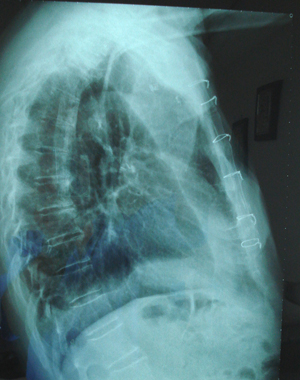

Εικόνα 2

Πλάγια ακτινογραφία θώρακος, ευμεγέθης μάζα στο οπίσθιο-μέσο-άνω πνευμονικό πεδίο, με ομοιογενή σύσταση και ομαλά όρια.